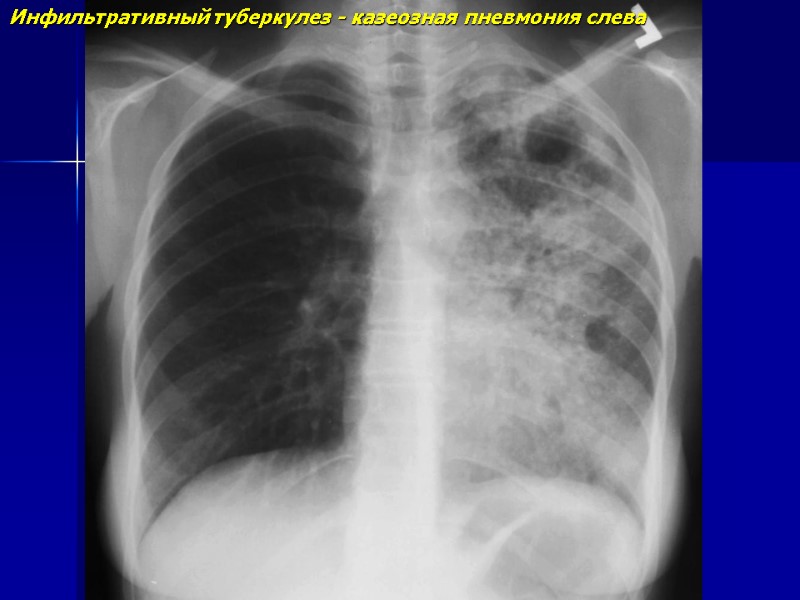

Инфильтративный туберкулез - казеозная пневмония слева